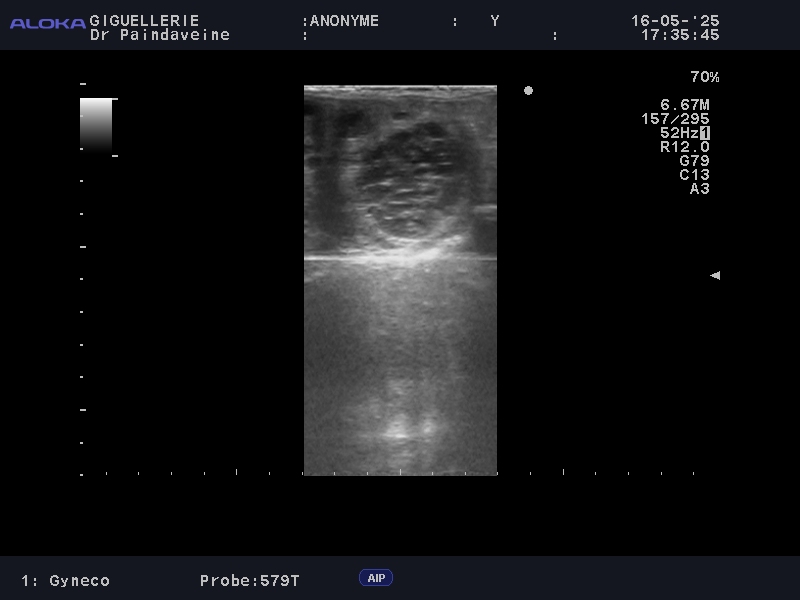

• Eierstöcke: Überwachung der Follikeldynamik zur Vorhersage des Eisprungs und zur Erkennung funktioneller Anomalien (persistierende Gelbkörper, Zysten).

• Gebärmutter: Kontrolle des Tonus und der Gebärmutterumgebung. Besonderes Augenmerk legen wir auf das Fehlen übermäßiger postovulatorischer Ödeme oder Endometritis, die Hauptfaktoren für frühe Resorptionen sind.

Während die Besamung mit Frisch- oder Kühlsperma eine gewisse Flexibilität bietet, erfordert der Einsatz von Gefriersperma (TG) chirurgische Präzision. Da die Überlebenszeit kryokonservierter Spermien verkürzt ist, wird die Überwachung intensiviert, um eine Besamung so nah wie möglich am Eisprung zu gewährleisten.